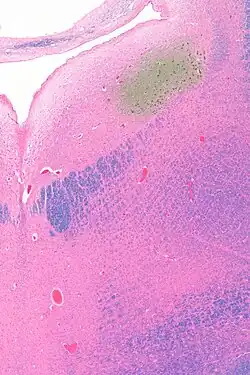

Anatomy

The locus coeruleus (LC) is located in the posterior area of the rostral pons in the lateral floor of the fourth ventricle. It is composed of mostly medium-size neurons. Melanin granules inside the neurons contribute to its blue colour. Thus, it is also known as the blue nucleus, or the nucleus pigmentosus pontis (heavily pigmented pontine nucleus).[5] The neuromelanin is formed by the polymerization of norepinephrine and is analogous to the black dopamine-based neuromelanin in the substantia nigra.

In adult human males,[a] the locus coeruleus has 22,000 to 51,000 total pigmented neurons that range in volume from 31,000 to 60,000 μm3.[6]